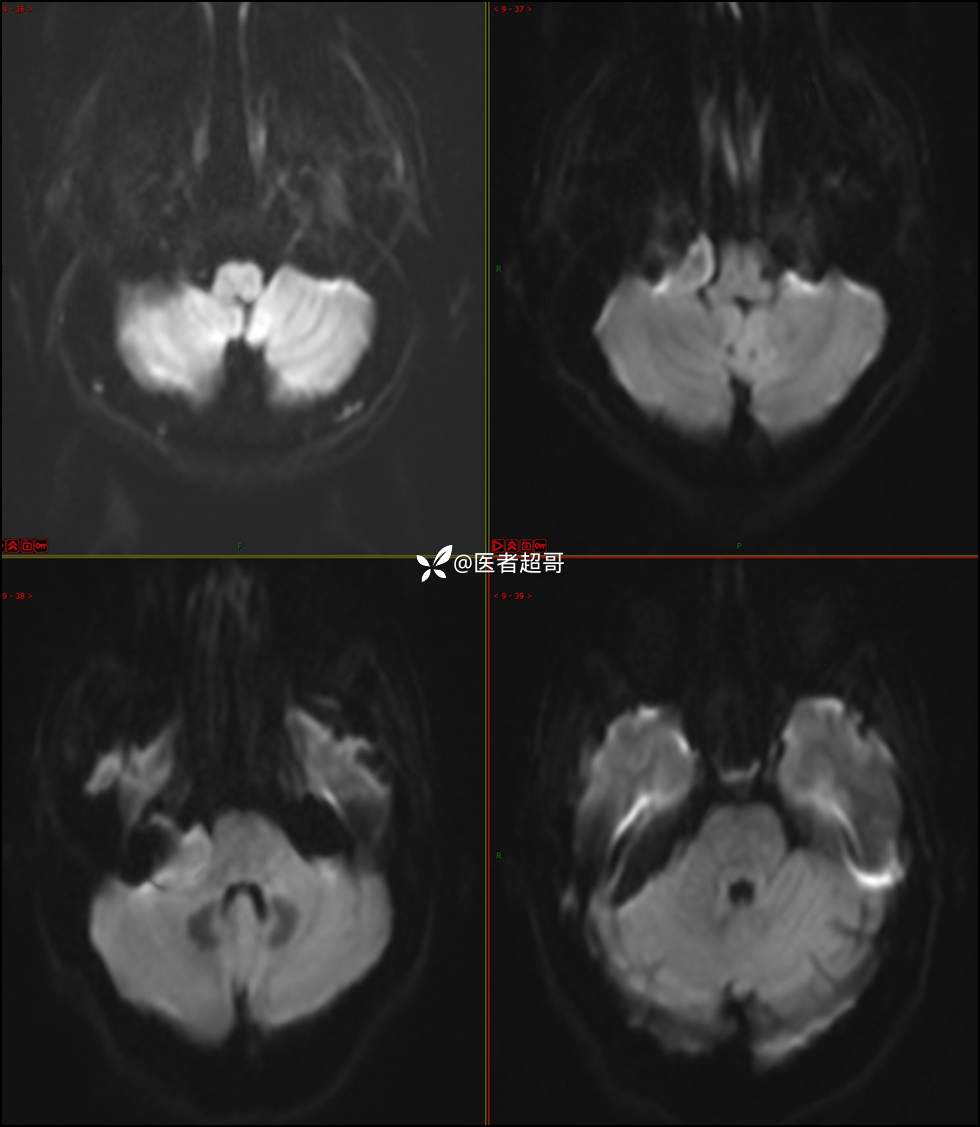

CPA区占位,是鞘瘤?脑膜瘤?请赏析!

现病史:患者3年前出现耳鸣,蝉鸣音,反复发作,夜间自觉明显,于2018年8月至我院耳鼻喉科就诊,行颅脑CT检查未发现明显异常改变,给予对症处理(具体不详);4天前突发头晕,伴明显恶心,至市人民医院就诊,行颅脑CT未见明显异常,颅脑MRI发现右侧桥脑小脑角区占位性病变。本次发病来无明显头痛,无肢体抽动,无大小便失禁。为求进一步诊治,遂来我院门诊,以“听神经良性肿瘤”收住入院。发病来,患者神志清,精神可,二便正常,饮食可,睡眠不佳,近期体重无明显变化,否认癫痫发作病史。